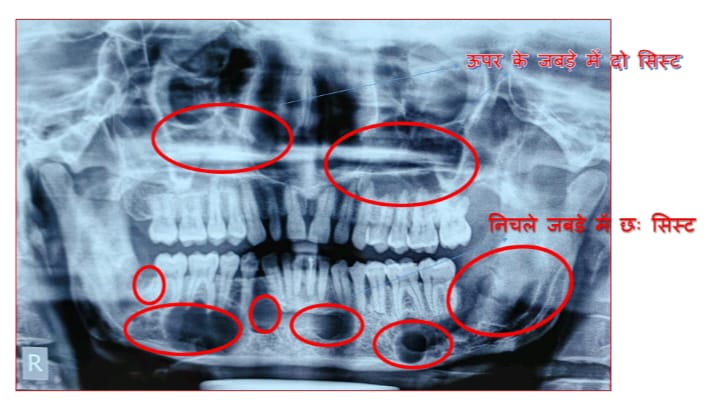

बिलासपुर/छत्तीसगढ़ आयुर्विज्ञान संस्थान के दन्त चिकित्सा विभाग द्वारा दुर्लभ बीमारी गोर्लिन गोल्त्ज़ सिंड्रोम से ग्रसित व्यक्ति की बीमारी का डायग्नोसिस कर सफल ऑपरेशन किया गया। कोरबा जिले के 35 वर्षीय मरीज रमेश यादव पिछले एक से डेढ़ साल से अलग अलग जगह इलाज करवाते रहे किन्तु फिर भी उसे समुचित उपचार नहीं मिला, क्योंकि कोई सही डाइग्नोसिस ही नहीं कर पाया। उल्लेखनीय है कि यह बीमारी अत्यंत दुर्लभ है और इसका डाइग्नोसिस करना भी उतना ही कठिन है। मरीज रमेश यादव सिम्स के दन्त चिकित्सा विभाग आने के बाद सबसे पहले मरीज का हिस्ट्री लिया गया, फिर फिजिकल एग्जामिनेशन किया गया। कुछ एक्स-रे लिया गया, बाईओप्सी की गई, इससे सम्बंधित ऑनलाइन डाटा सर्च किया गया। तत्पश्चात इस बिमारी को डाइग्नोस किया गया। जिसमे दन्त चिकित्सा विभाग के डॉ जण्डेल सिंह ठाकुर एवं डॉ केतकी कीनीकर ने महत्वपुर्ण भूमिका निभाई।

गोर्लिन गोल्त्ज़ सिंड्रोम बीमारी जो कि बहुत ही दुर्लभ है। भारतीय मरीजों में 1960 से लेकर अब तक 48 मरीजों में गोर्लिन गोल्त्ज सिंड्रोम बीमारी होने के लक्षण मिले। जिनमे से केवल 38 मरीज ही गोर्लिन गोल्त्ज सिंड्रोम के कन्फर्म हुए हैं। जिनका इलाज मुंबई, दिल्ली, बंगलौर जैसे शहरों में हुआ। गोर्लिन गोल्त्ज़ सिंड्रोम को डाइग्नोस करने के लिए अपनाई जाने वाली विधि में या तो 2 मेजर एवं एक माइनर क्राइटेरिया अथवा एक मेजर एवं 2 माइनर क्राइटेरिया का होना बहुत ही आवश्यक है। हमारे मरीज में तीन तरह के मेजर क्राइटेरिया पाए गए।

सिम्स के दन्त चिकित्सा विभाग द्वारा मरीज के दोनों जबड़े से मल्टीपल जॉ सिस्ट को निकाला गया तथा कॉरनॉय शोलयूशन से डिसइंफेक्ट किया गया। अवगत हो कि ऐसे जॉ सिस्ट के रेक्यूरेंश रेट काफी हाई होते जो कि 60 प्रतिशत तक होते हैं। ऑपरेशन के बाद मरीज एक हफ्ता भर्ती रखकर इलाज किया गया। मरीज यहाँ के इलाज से पूरी तरह संतुष्ट है। इन मरीजों को हर 6 महीने में दिखते रहना चाहिए क्योकि इनमे मेलिग्नेन्सी होने की प्रबल सम्भावना होती है।